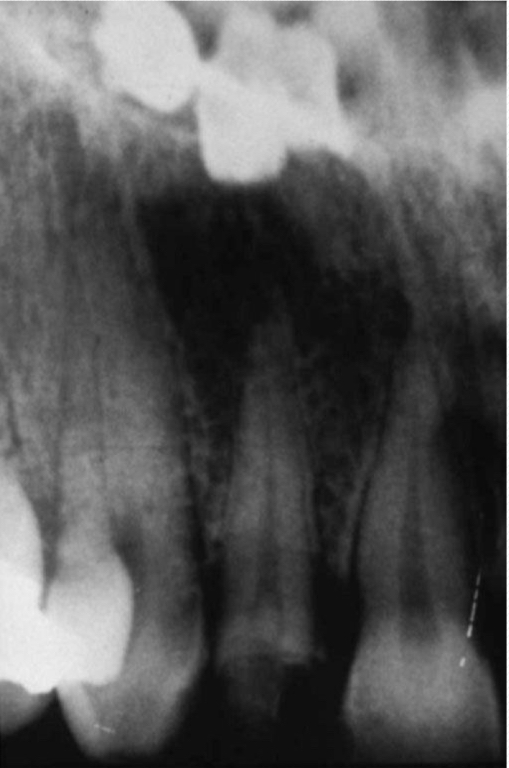

Post and core

All porcelain restorations:

Resembles radiopacity of dentin

Porcelain-fused-to-metal crown (PFM)

PFM bridge

Gutta percha

Silver points